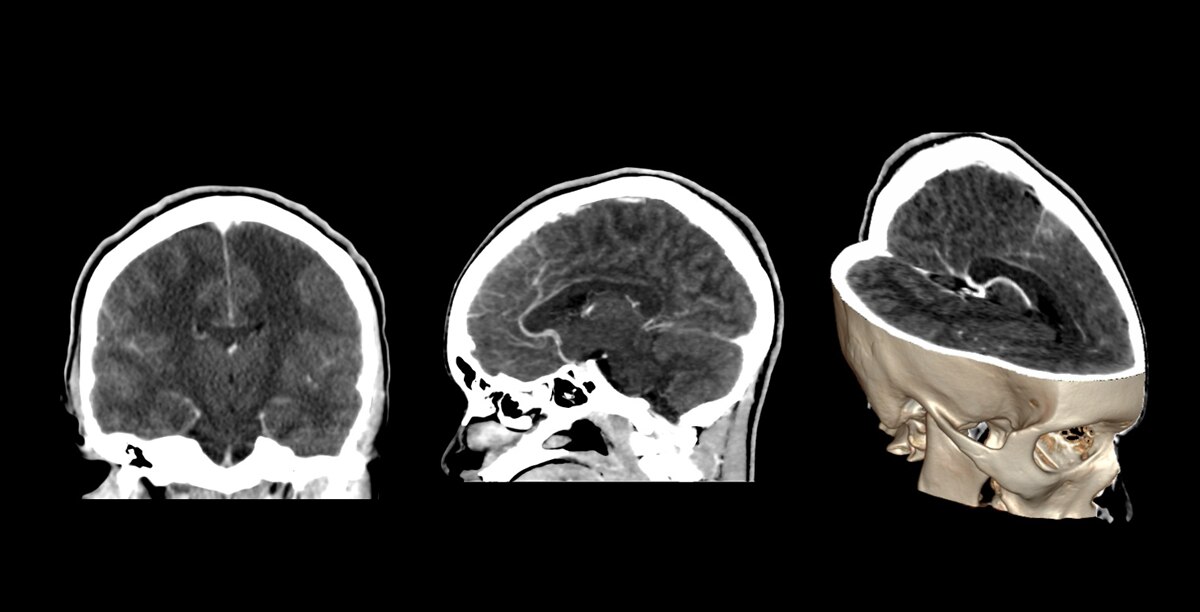

Circle of Willis